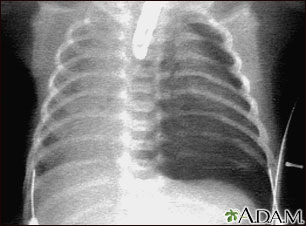

Neumotórax, radiografía de tórax

El neumotórax ocurre cuando se filtra aire desde el interior del pulmón hacia el espacio entre el pulmón y la pared torácica, ocasionando un colapso del pulmón. La oscuridad al lado derecho de la imagen indica la presencia de aire fuera del tejido pulmonar.